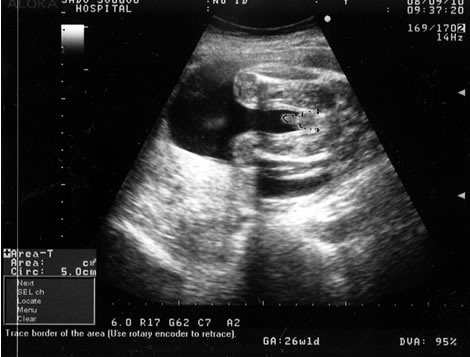

妊娠26週目に入った嫁。 今日は妊婦検診の日。

そろそろ性別も分かる頃なんだけど、心配なのは、最近お腹が張るらしいこと。

のん子の時には切迫早産の危機で、何度も入退院を繰り返したので、その事が頭をよぎるわけですよ。

こうなったら、オイラも負けるわけにはいかない訳で、「エコーあるんでしょ? 帰ってからゆっくり見るよ」 っと余裕を装う。

帰って早速、もったいぶりながら出されるエコーを凝視する!

凝視する!!! (ほら、エコーって分かりづらいしさぁ)

性別はどっち?

・・・・・んっ?!

こっ、これはっ!!!!

チン○ーっっ!!

これが尻尾だったりしなければ、多分男の子。

女系家族の中で、ついにオイラに味方が出来そうです!

んー、Xデイは12月。 早くもドキドキです。